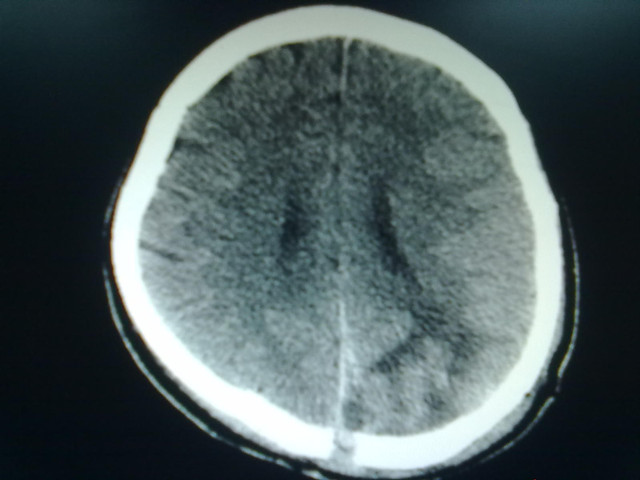

患者术后神志仍处于昏迷状态,出现不稳定发热,右侧肢体瘫痪无缓解。经全科讨论,确定辅以中医中药疗法,经合参四诊,患者罹病属中医学之“中风-中经络”范畴,病位在脑脉,病性本虚标实,治以息风化痰,化瘀通络为法,方拟化痰通络汤加减。经过一周的中药方剂治疗,患者头痛等症状明显改善,神志逐渐清醒,语言、记忆力及视力恢复正常,四肢肌力Ⅴ级,能自立行走。

术后复查